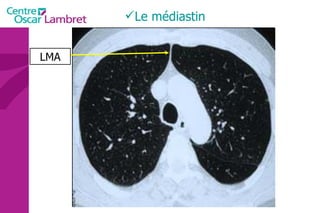

Le médiastin

La ligne médiastinale antérieure (jonction des deux languettes pulmonaires antérieures avec 4 feuillets pleuraux en arrière du sternum et en avant du médiastin).  •  La ligne médiastinale postérieure (jonction des deux languettes pulmonaires postérieures et supérieures en arrière du médiastin). Le médiastin

Le médiastin LMA

Le médiastin LMP

Ligne médiastinale postérieure Ligne médiastinale antérieure Le médiastin